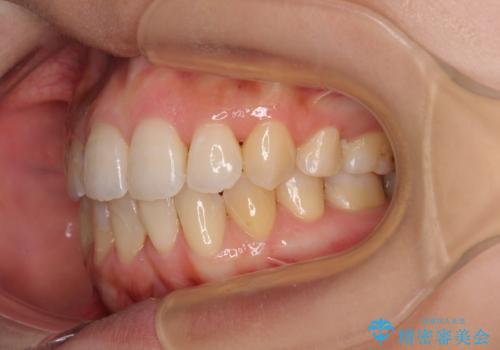

後戻りの再矯正 ワイヤー装置でデコボコと隙間を改善

- 学生時代の抜歯矯正の後戻りが気になり、再矯正を希望して来院された患者様です。

マウスピース矯正は継続する自信がなく、気になるところを短期間で改善したいとのことで、ワイヤー装置にて矯正治療を行うこととしました。

詰め物で隠していた下顎前歯の隙間は、歯軸を改善することで詰め物を除去しても隙間が目立たなくなりました。

まだ改善したいところはありましたが、患者様自身は大変満足されたとのことで、治療を終えることとなりました。